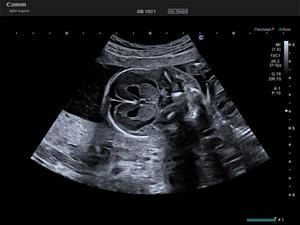

近年,女性の社会進出や生活習慣の変化に伴い,乳がんや卵巣がん,子宮筋腫などの疾患リスクが高まっている。また,晩婚化による出産年齢の高齢化により,先天性疾患や胎児発育遅延(FGR),前置胎盤などのリスクも増加している。「Aplio beyond / Women’s Healthモデル」は,これらの課題に対応するために開発された超音波診断装置。高精細な画像描出,微細な血流の観察,多彩なアプリケーションを搭載し,女性関連疾患の早期発見・診断を強力にサポートする。

Bモード画像内でRAWデータ信号の隣り合った輝度の連続性を分析し,高性能なGPU/CPUによって画像処理を行う。飽和し滲んだ箇所はシャープに表現し,信号強度が低い箇所は輝度補完を行い,バランスを整え,組織の境界および構造をシャープに描出する。さらにスペックルとして表示される実質部分は細かさを残しながら均一に,かつ実質内の細かな血管などの構造を残しながら表示して高分解能な画像を提供する。この処理を連続するフレームに対して適用することで,自然な残像感を提供し,空間の認識力を向上させた観察が期待される。

Precision Plus Fine Processing mode(PPFP)の比較イメージ

PPFP:OFF |

PPFP:ON |